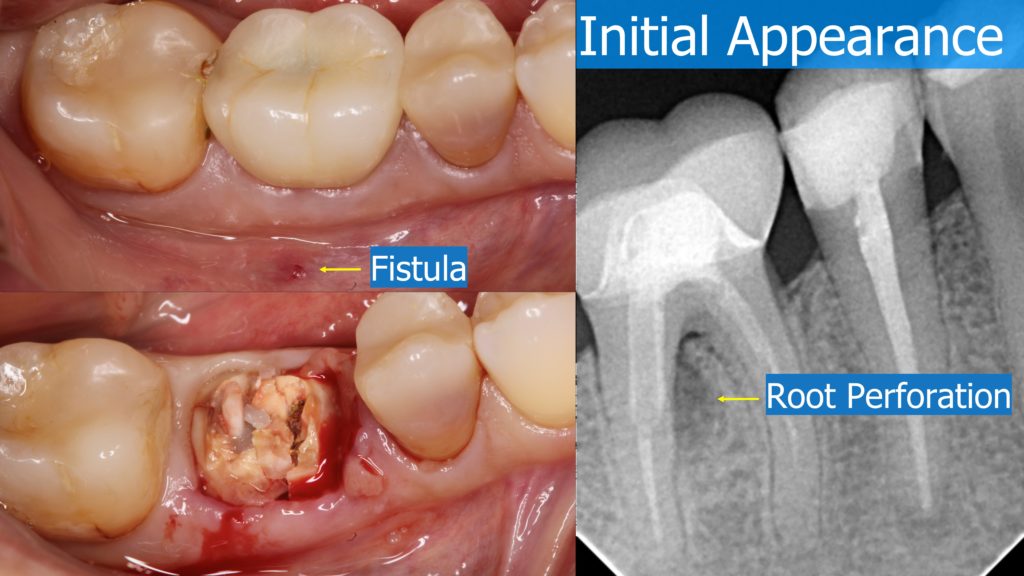

A healthy 36 year old woman comes to the clinic with pain and swelling in the area of the inferior left molars. In the intraoral observation, a vestibular fistula was identified, and the complementary exams confirmed a bone lesion caused by a root perforation (poorly executed false post) on the first lower left molar #36 (19). It was decided to do antibiotic therapy for a week and then the tooth extraction with immediate implant placement and bone graft. 4 months post-op the definitive zirconia/ceramic crown would be was made.